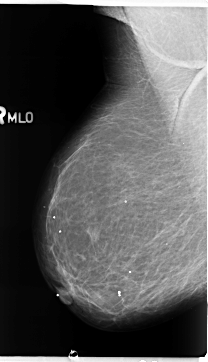

B_3099_1.RIGHT_MLO

RIGHT_MLO LINES 4704 PIXELS_PER_LINE 2696 BITS_PER_PIXEL 12 RESOLUTION 50 NON_OVERLAY